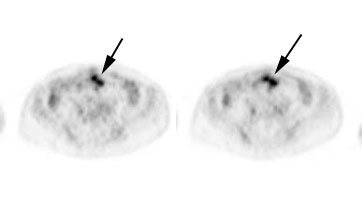

Recurrent colorectal cancer: The patient shown below had a history of colon cancer and a rising CEA level. FDG PET exam revealed a site of tracer uptake in the mesentery (black arrows) which corresponded to an enlarged lymph node seen retrospectively on CT scan (white arrow). |

|